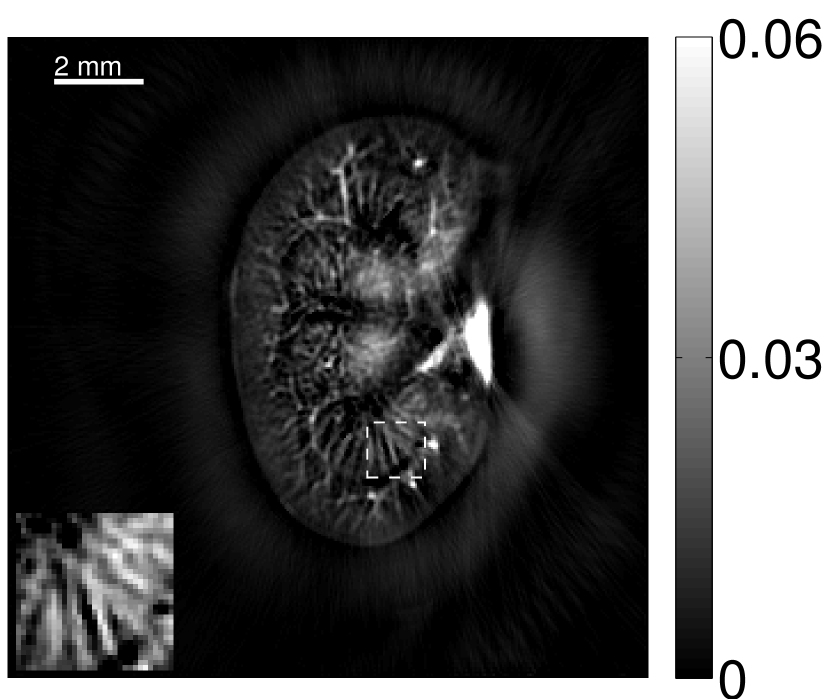

VI-E Results: kidney phantom

The images and EIRs reconstructed by use of the VP algorithm that was based on the 2D imaging model that neglected the SIR are shown in Figures 15 and 16. The latter figure contains results corresponding to different values for the regularization parameter . From Fig. 15, it can be observed that use of the conventional iterative method that utilized the measured EIR resulted in distortions and loss of details in the reconstructed images. Use of the VP algorithm improved the contrast and the details in the reconstructed images (Fig. 15(c) and 16(a)). Furthermore, the images reconstructed by use of the VP algorithm had a more uniform background.

In Figure 17, the results corresponding to use of the 3D imaging model that incorporated SIR effects are shown. The EIR estimated by the VP algorithm is also shown. In Figure 18, images and EIRs reconstructed by use of the VP algorithm with different regularization parameters values are shown.

Similar to the case described above where the transducer SIR was neglected, these results reveal that use of the VP algorithm can produce images with a cleaner background and enhanced spatial resolution than yielded by use of a conventional iterative algorithm that employed the measured EIR. For example, detailed information regarding the vessels near the organ’s periphery was better preserved by the VP algorithm than by the conventional iterative algorithm. These images corroborate our assertion that the VP algorithm can significantly reduce the artifacts and distortions in the reconstructed image. It is also worth pointing out that, unlike the numerical phantom studies, the artifacts and distortions in the images may be caused not only by the inaccurate EIR but also by other factors, such as neglecting acoustic heterogeneities and the variation of the EIRs among the elements of the transducer array. In such cases, the EIR estimated by the VP algorithm represents an effective system impulse response that minimizes the inconsistency between the measured data and the imaging model.